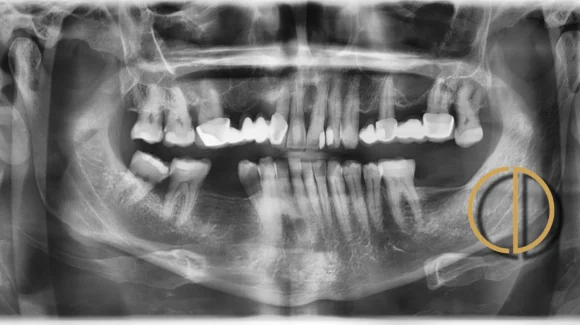

Páciensem eredetileg ultrahangos fogkőeltávolításra érkezett dentálhigiéniai szakrendelésünkre. A vizsgálat során azonban jelentős mennyiségű fogkő, ínyrecesszió és fogszuvasodás gyanúja merült fel, ezért részletes fogászati állapotfelmérésre irányították hozzám.

A páciens utoljára körülbelül 4 évvel korábban járt fogkőeltávolításon, míg fogorvosi szűrővizsgálaton legalább 9 éve nem vett részt. Panaszai nem voltak, ami gyakori jelenség: a fogágybetegség és a régi fogpótlások problémái sokszor hosszú ideig tünetmentesen zajlanak.

A felső fogsorban található hídpótlások (12–16 és 24–27 között) több mint 20 évesek voltak.

- kiterjedt kopást,

- lepattant kerámiarészeket,

- a pótlások széli záródásánál szuvasodás jeleit észleltük, ezért a pótlások cseréje szakmailag elkerülhetetlenné vált.

A diagnózis részeként jelentős ínyvisszahúzódást és több fog mozgathatóságát is megállapítottuk, ezért a páciens parodontológiai konzultáción is részt vett. A fogágykezelés nemcsak a gyulladás megszüntetése miatt volt fontos, hanem azért is, hogy pontosan meghatározzuk, mely fogak tarthatók meg a fogpótlási tervben.